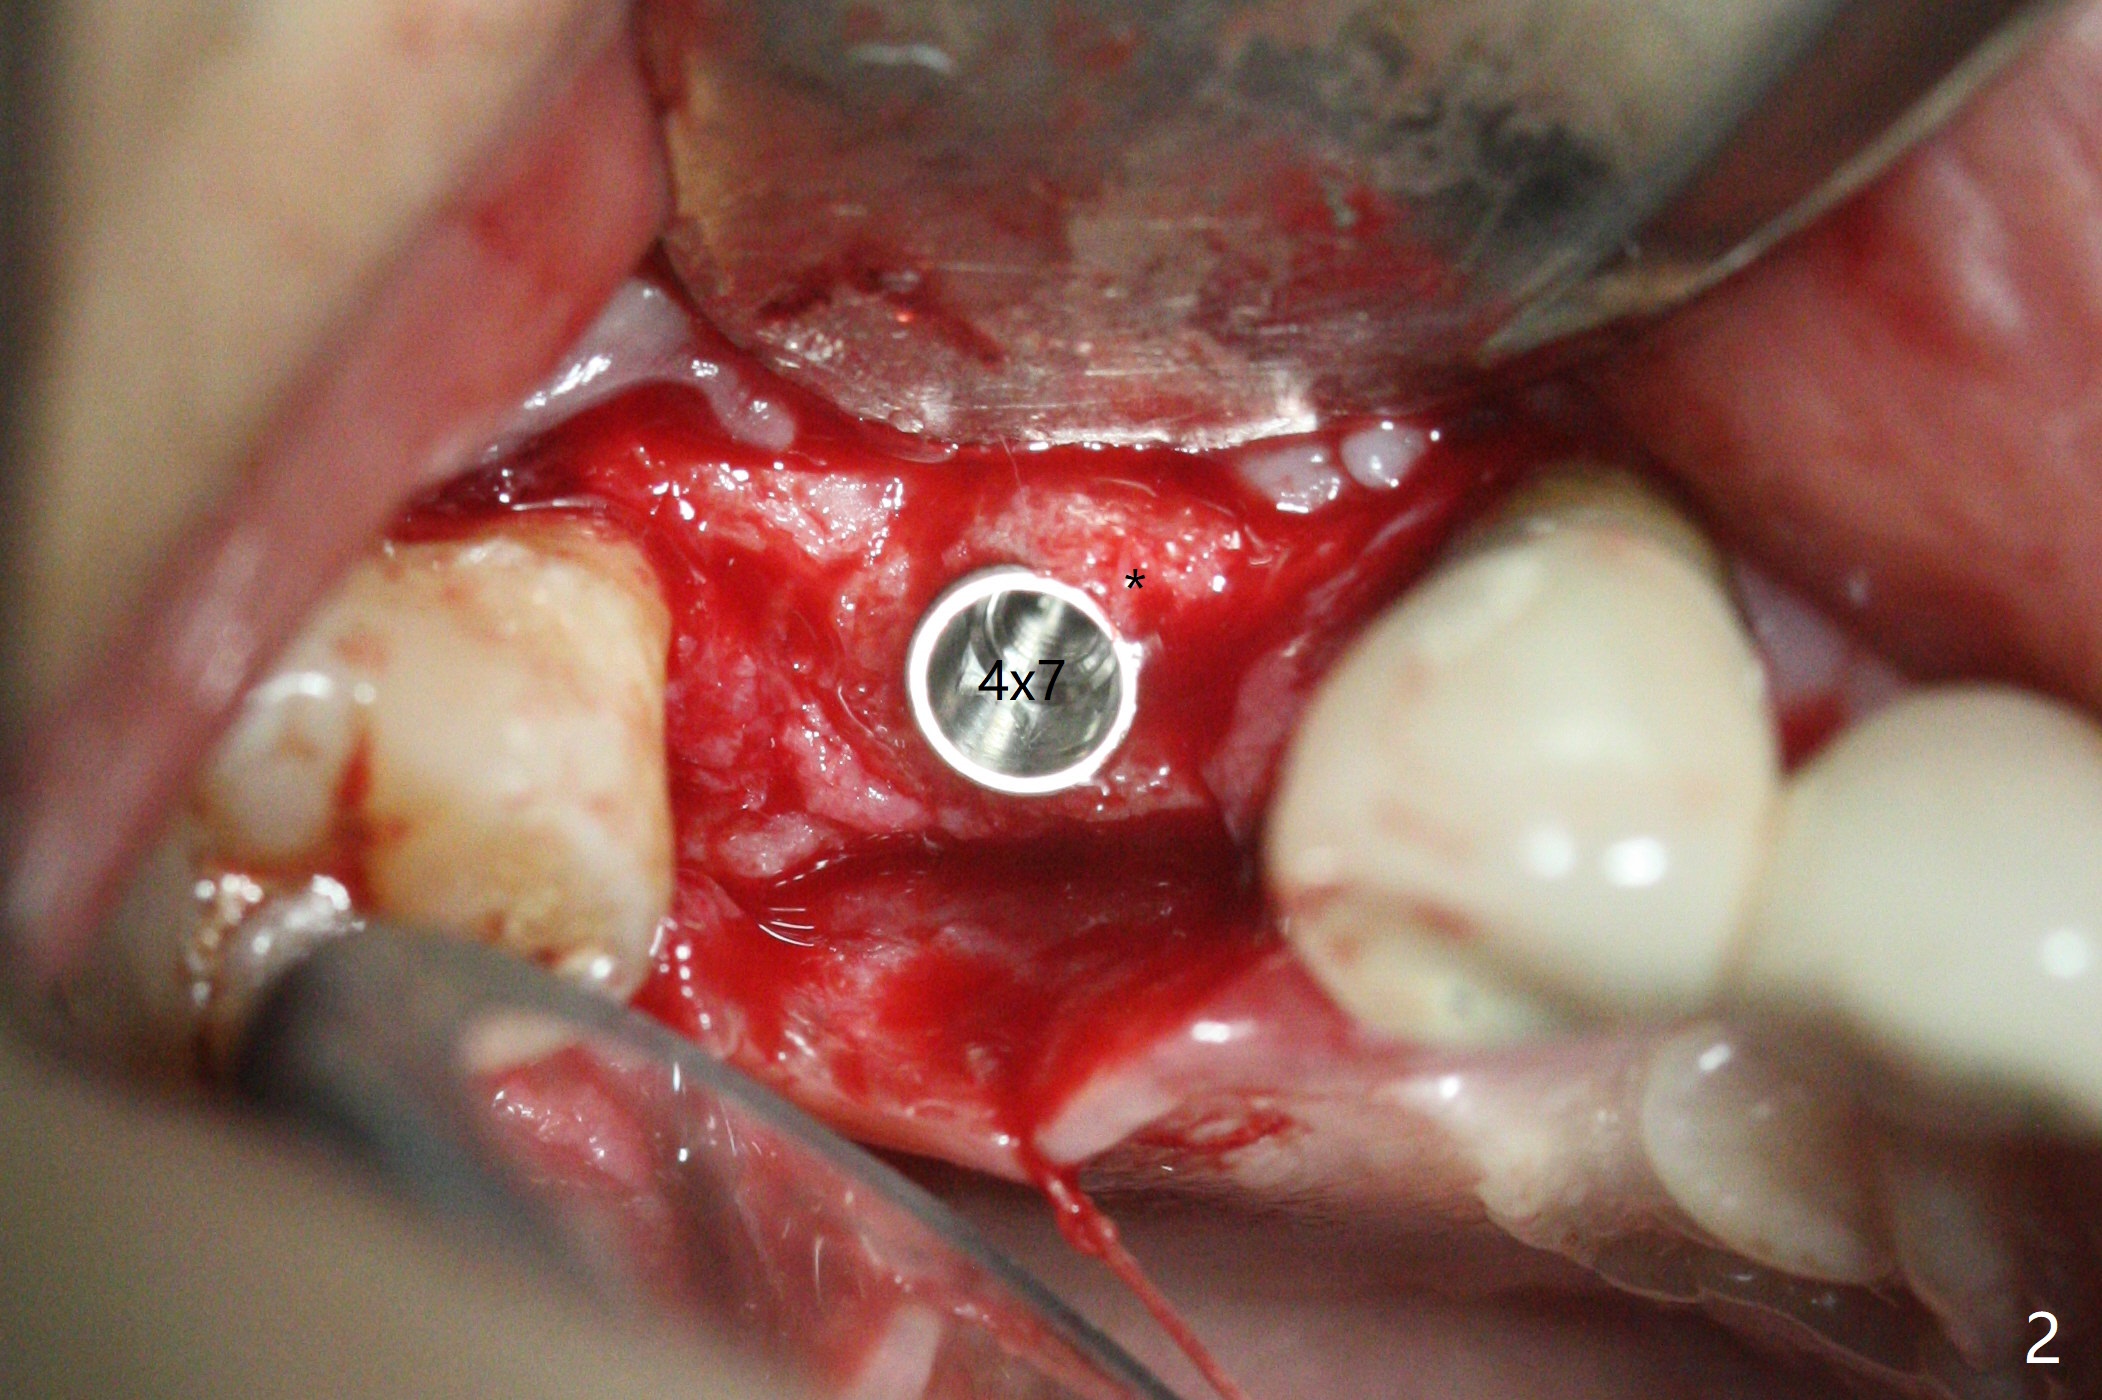

49岁女(个子小)牙齿问题多,同意先做右上5,6种植,6骨质高度1-2毫米,一个月前因动脉出血外提升失败。今天她回来做内提升,同意如果条件合适,同期徒手植牙(将来做一个磨牙牙冠),事先服用阿奇霉素。使用粘性骨粉和报废植体做内提(图一:*),最后植入4x7毫米植体(35Ncm),近中颊侧平牙槽嵴(图二:*),其余骨上 (图三: *),不敢植入太深,怕掉入上颌窦。第二个预防掉入上颌窦措施是利用大号基台(图三),然后在基台周围放置骨粉(图四:*,五),缝合,牙周敷料。伤口愈合后,准备制作树脂敷料,防止植体和基台往口腔脱落。术后五天复诊,无上颌窦炎症,牙周敷料稳定。她再回来时已经术后4.5个月,植体稳定,更换基台没有疼痛(图六,七),口腔卫生极佳,使用水牙线,不敢患侧刷牙。